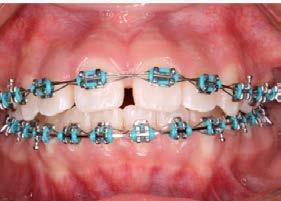

Higiene oral, autopercepción estética y confort en pacientes con ortodoncia

Introducción: Los principales objetivos del tratamiento ortodóncico son corregir las maloclusiones y mejorar la estética dental; sin embargo, el mismo tratamiento puede asociarse a reacciones negativas al requerir aparatología visible que altera aspectos funcionales, estéticos y de higiene oral del paciente. Estos factores podrían influir en la motivación del paciente y determinar una baja adherencia al tratamiento ortodóncico, lo que podría generar retrasos y complicaciones en la estabilización de la oclusión. Objetivo: Evaluar el nivel de satisfacción del paciente con brackets en relación con la higiene oral, el confort y la autopercepción estética. Metodología: Se trata de un estudio transversal con muestreo por conveniencia. Se evaluó el nivel de satisfacción relacionado con la higiene oral, la autopercepción estética y el confort de pacientes tratados en el Instituto mediante un cuestionario validado de autorreporte. Se realizó un análisis descriptivo de la muestra y el cálculo del puntaje del cuestionario; posteriormente, se efectuó un análisis bivariado entre las variables edad, sexo, tratamiento previo y tiempo bajo tratamiento

ortodóncico. Resultados: Participaron 74 pacientes con una edad promedio de 27.1 ± 8.2 años. El 55.4% (n = 41) fueron mujeres. Los hombres presentaron un menor nivel de satisfacción ( = 33.2 ± 6.4) que las mujeres ( = 35.2 ± 8.2). Aquellos pacientes que recibían tratamiento de ortodoncia por primera vez obtuvieron un menor puntaje —y, por tanto, un menor nivel de satisfacción— ( = 33.4 ± 7.6) que quienes ya habían estado sometidos a este tratamiento ( = 35.2 ± 4.6). Los pacientes con hasta 1 año de tratamiento mostraron un menor nivel de satisfacción ( = 33.2 ± 4.6) que aquellos con aparatología por más de 1 año ( = 35.1 ± 3.1). Conclusión: Es importante evaluar, en cada paciente, los factores que puedan influir de forma negativa en su calidad de vida a lo largo del tratamiento, con la finalidad de plantear intervenciones efectivas enfocadas en crear conciencia sobre las expectativas y los posibles inconvenientes derivados del mismo.

Palabras clave: satisfacción, estética, confort, higiene, brackets.

C.D. Octavio Bautista López*, M. en C. José Cuauhtémoc Jiménez Núñez*°, Esp. Gustavo Castillo Salazar* *Instituto de Ortodoncia Bioprogresiva °Facultad de Estudios Superiores Iztacala